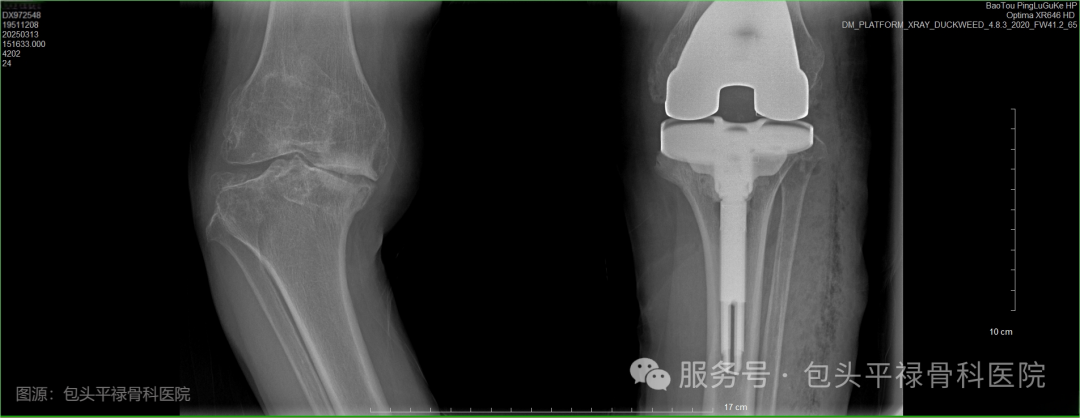

单侧人工膝关节置换术后

顾名思义,是指通过手术将受损的膝关节部分或全部替换为人工关节,以恢复关节功能、缓解疼痛和改善生活质量。医生会移除严重磨损的关节部位,在原位安装上与原始膝关节表面形状类似的假体,使用骨水泥使假体与患者自身的股骨和胫骨固定在一起,从而恢复膝关节的正常功能。

人工膝关节置换术前VS术后

老年患者左膝术前VS康复治疗仪VS患者术后复查